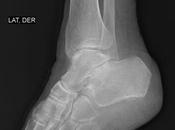

Fractura de peroné a nivel de maléolo, inferior a sindesmosis sin aparentes...

RADIOGRAFIA AP Y LATERAL DE TOBILLO LAS PROYECCIONES RADIOLOGICAS OBTENIDAS NOS MUESTRAN LOS SIGUIENTES HALLAZGOS -Tejidos blandos, con aumento la densidad y... Leer el resto